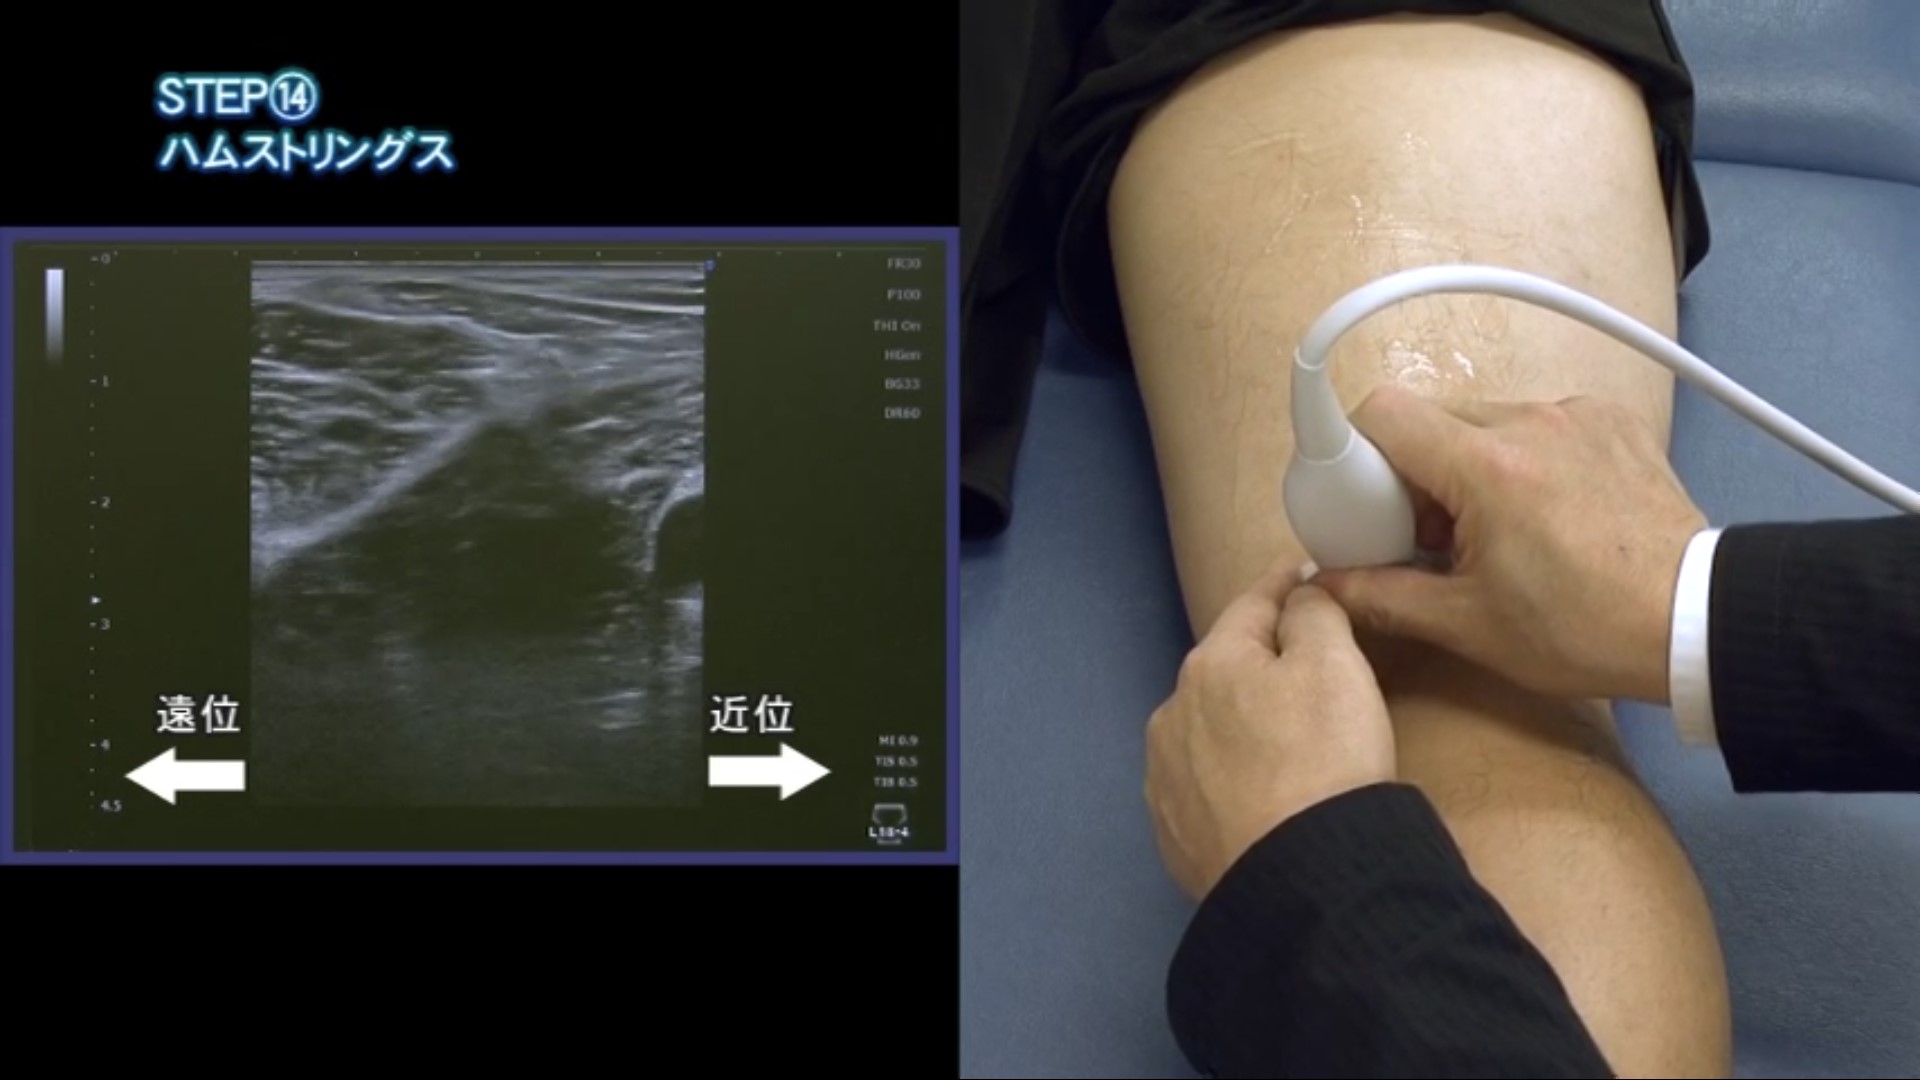

STEP(14) ハムストリングス

08分04秒